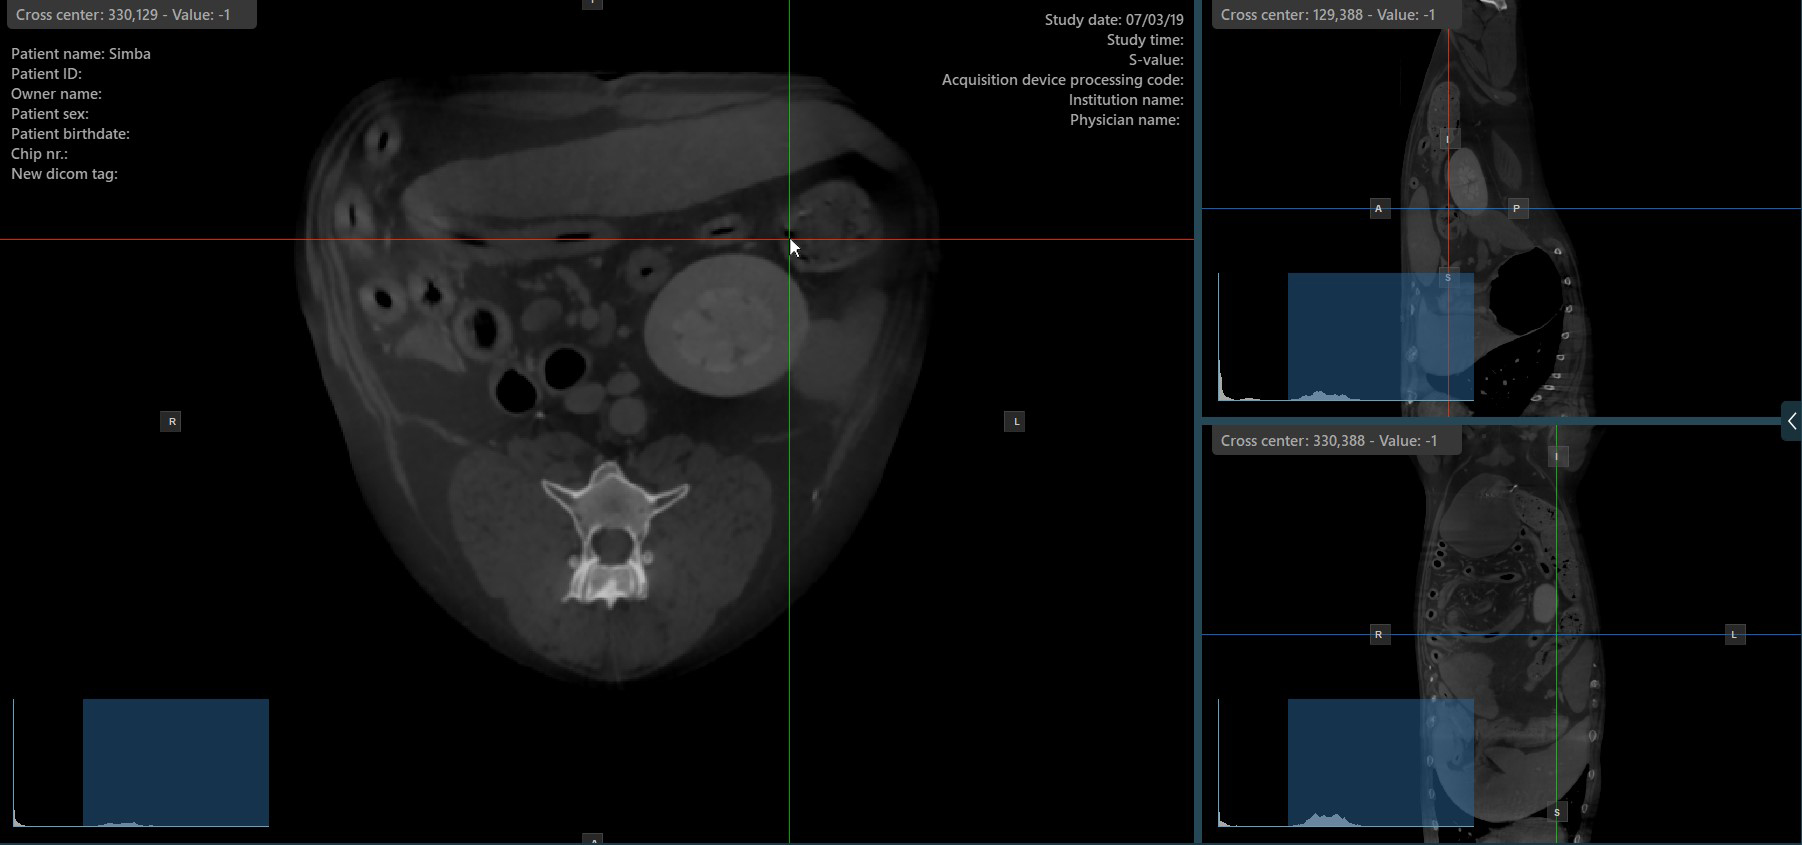

Show/Hide Slicers¶

By default, the slicers are visible on the top of the images. The corresponding icon in the left toolbar of the CT Viewer will be selected when the slicers are visible.

Press the Hide/Show Slicers icon the left toolbar to hide the slicers. The corresponding icon in the left toolbar of the CT Viewer will be deselected when the slicers are hidden.

Users can toggle the visibility of the slicers by using the Hide/Show Slicers option from the left toolbar, or using one of the Tools -> Hide Slicers or Tools -> Show Slicers options from the CT Viewer menu.